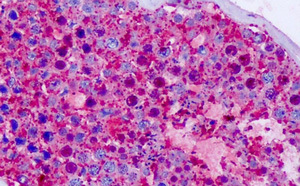

Supportive validation

- Submitted by

- OriGene (provider)

- Main image

- Experimental details

- Immunhistochemistry analysis in human tonsil (Formalin-fixed, Paraffin-embedded) using?CELSR1?antibody .? (C-term).

- Validation comment

- IHC